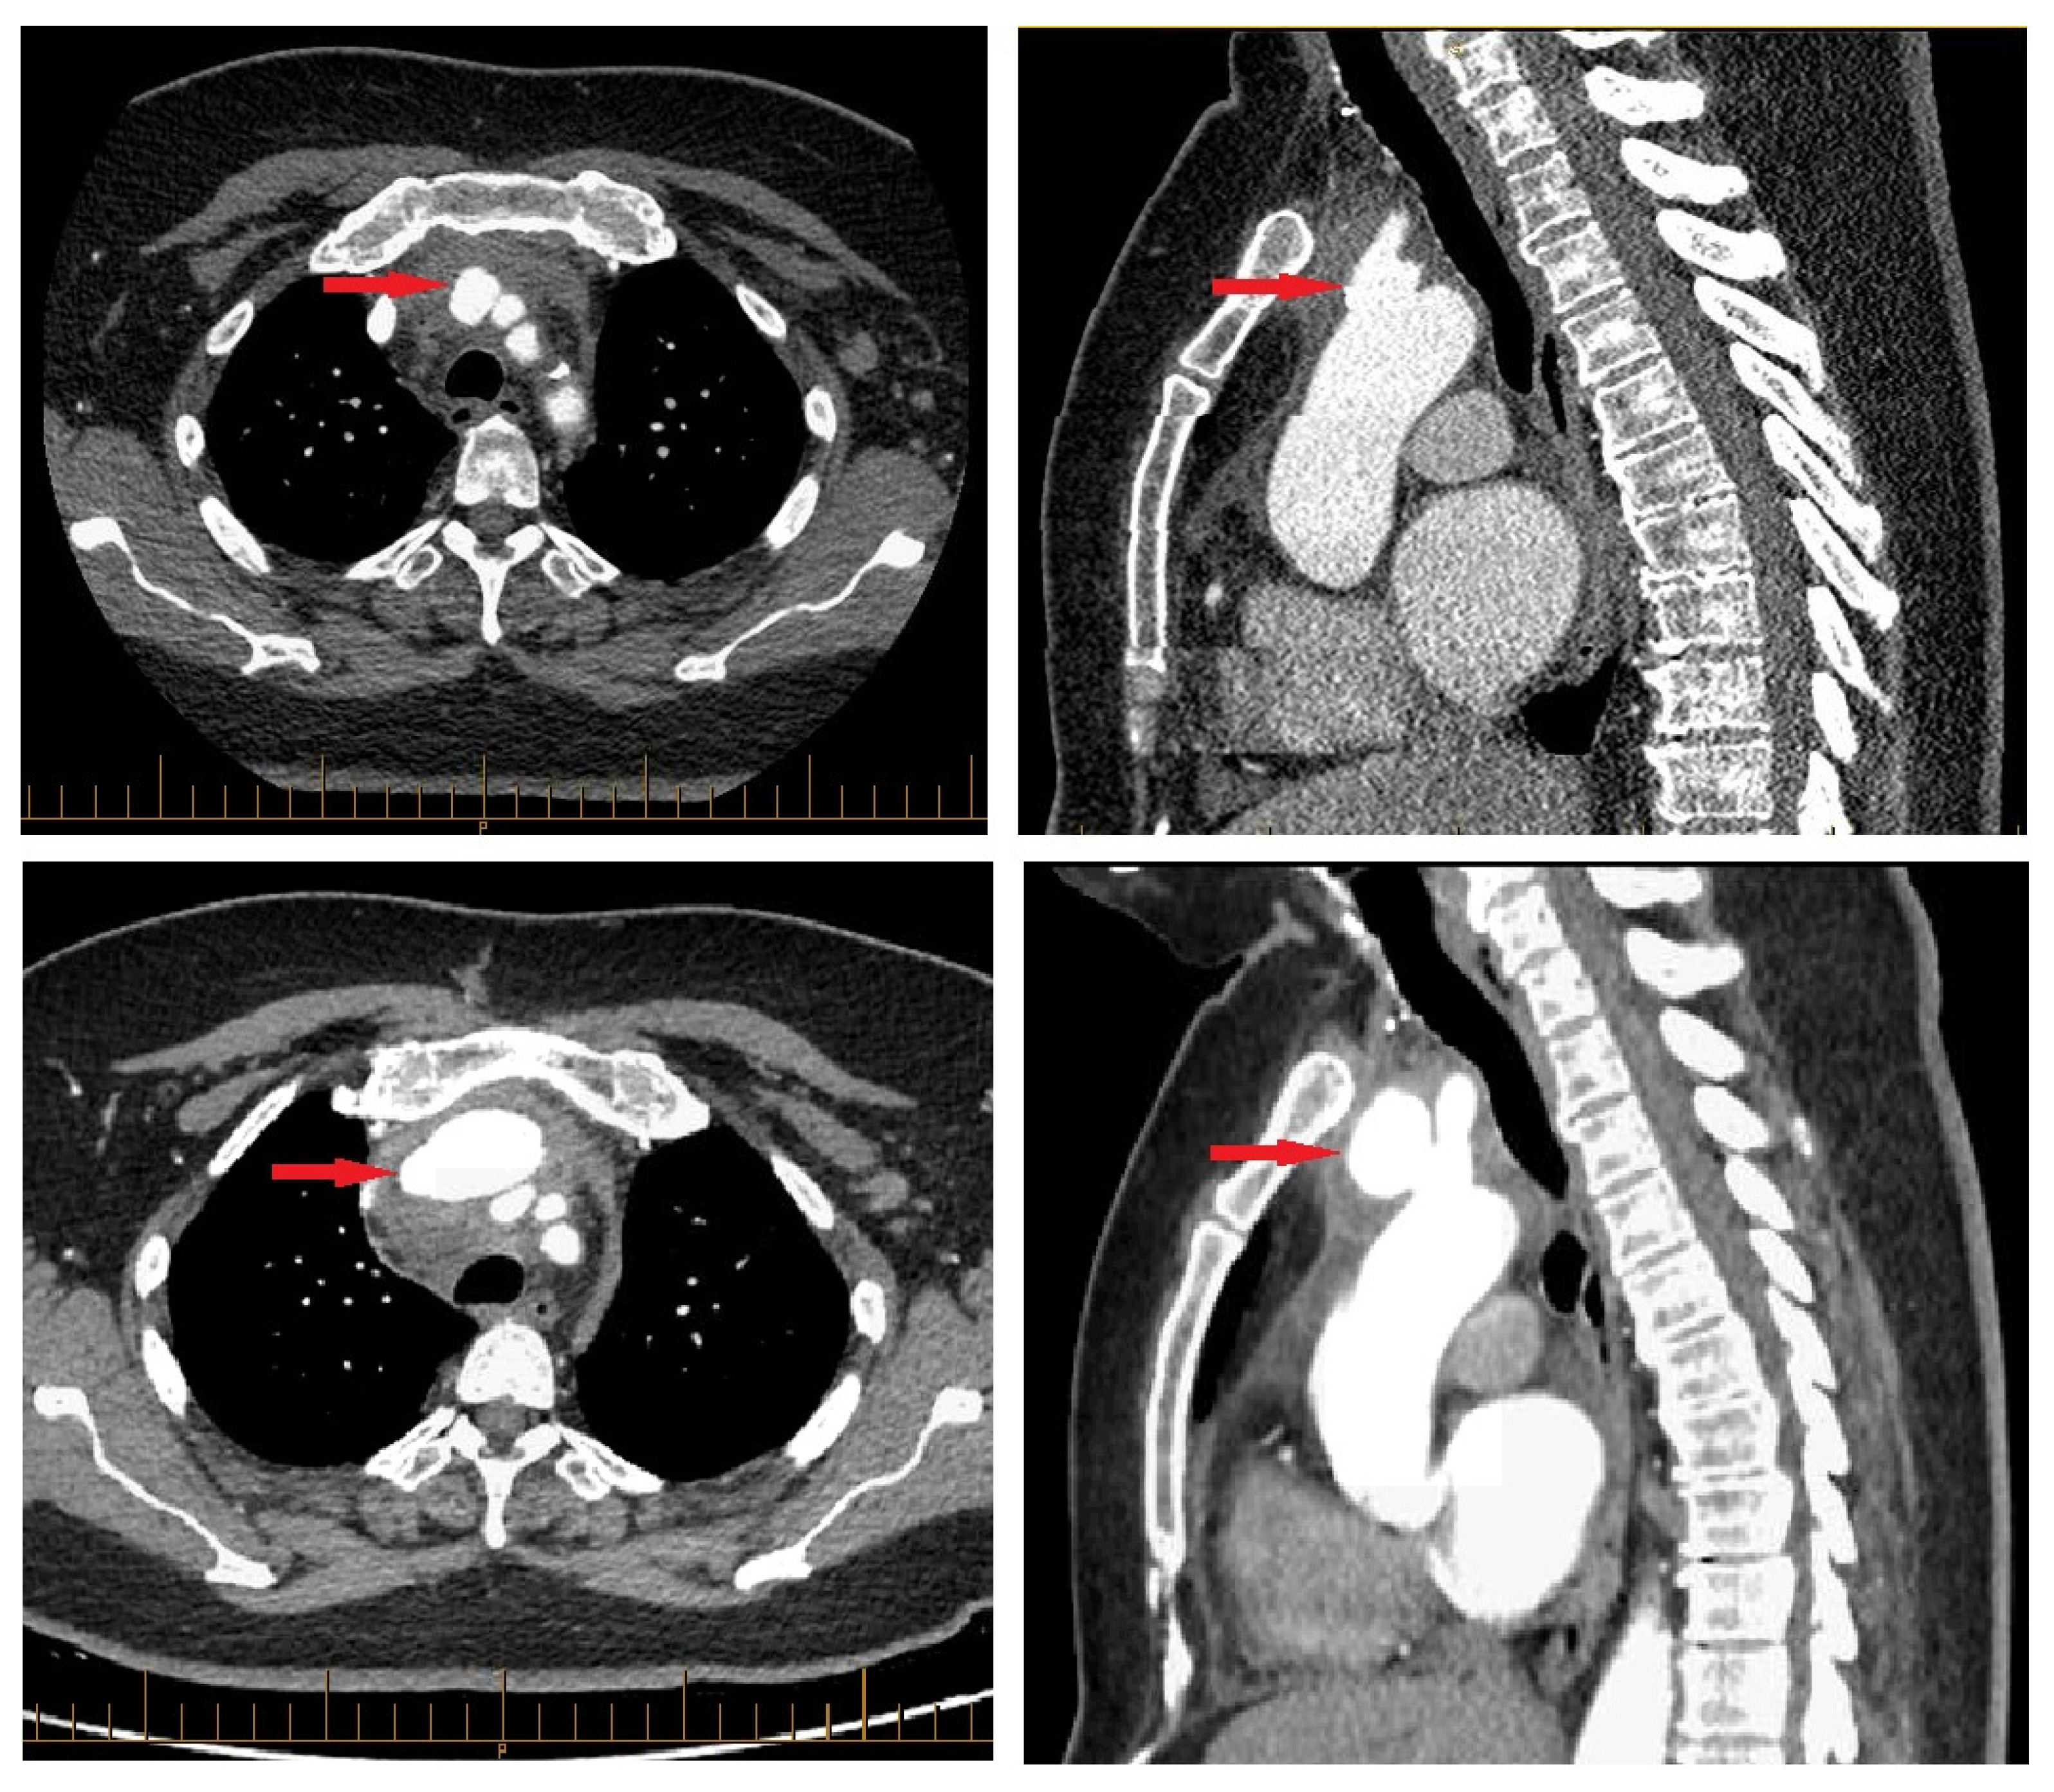

CT revealed a pseudoaneurysm (7 × 5.5 mm) at the common origin of the brachiocephalic trunk, and the left common carotid artery was incidentally found (Figure 1). Surrounding periaortic fat stranding and the presence of axillary and retro-pectoral lymph nodes suggested an infectious process. A transthoracic echocardiogram demonstrated normal cardiac chamber dimensions, preserved systolic and diastolic function (left ventricular ejection fraction 60–65%), and mild degenerative valvular changes without intra-cardiac vegetations or significant valvulopathy.

Inflammatory markers remained elevated but gradually declined, as did WBCs. Troponins peaked mildly within 5 days of admission (34.0 ng/L) and eventually normalized, as did TSH by discharge. After a satisfactory decline in infectious and inflammatory biological parameters under intravenous piperacillin–tazobactam, the decision was made to pursue outpatient parenteral antibiotics. However, a CT angiogram performed before the patient’s discharge three weeks after admission revealed an interval increase in the mycotic aneurysm (41 × 26 mm) (Figure 1). In light of this change, a staged surgical intervention was undertaken 2 weeks later.

Figure 1. Initial finding of pseudoaneurysm (red, top row) and sudden enlargement (bottom row).